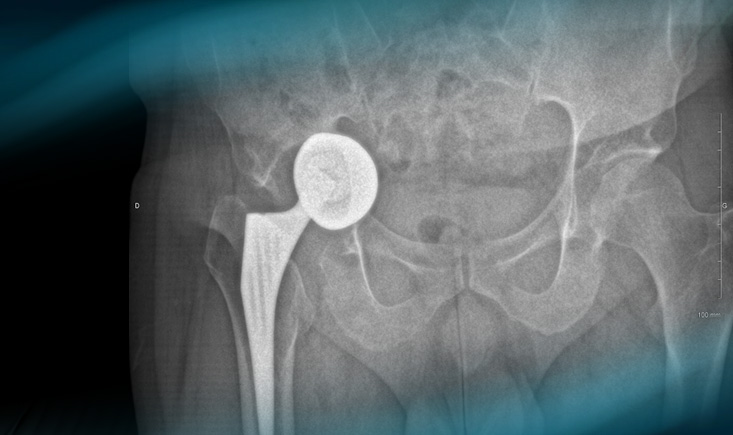

> 2 years imagery

Postoperative imagery